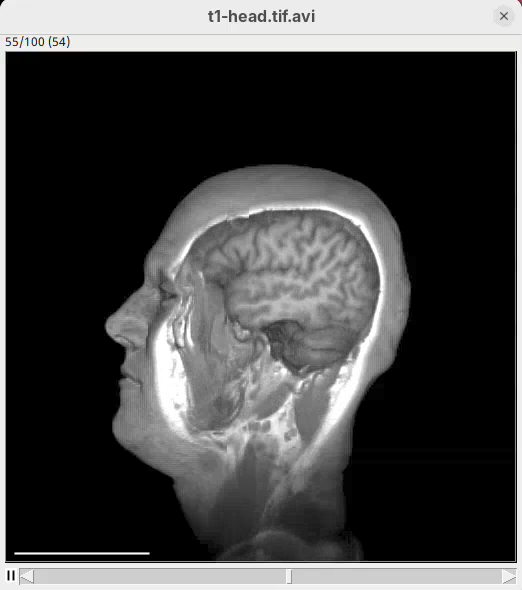

Animate cropping

Let’s add a couple more commands below our rotation sentence. We want that, after the 360 degree rotation, the animation slices through the head to show the tissues inside. For that, we can change the cropping parameters to control the position of the bounding box during the animation.

- After the first sentence, write the two commands as shown below:

From frame 0 to frame 35 rotate by 360 degrees horizontally

From frame 36 to frame 71 change channel 1 bounding box min z to 60

From frame 72 to frame 99 change channel 1 bounding box min z to 0- Press

Run.

The script is saying to rotate 360 degrees horizontally, as before, set the Z range minimum to 60 (roughly halfway through the sample) for about 30 frames, and then set the Z range minimum back to 0 in the subsequent 30 frames. And that’s what we get.